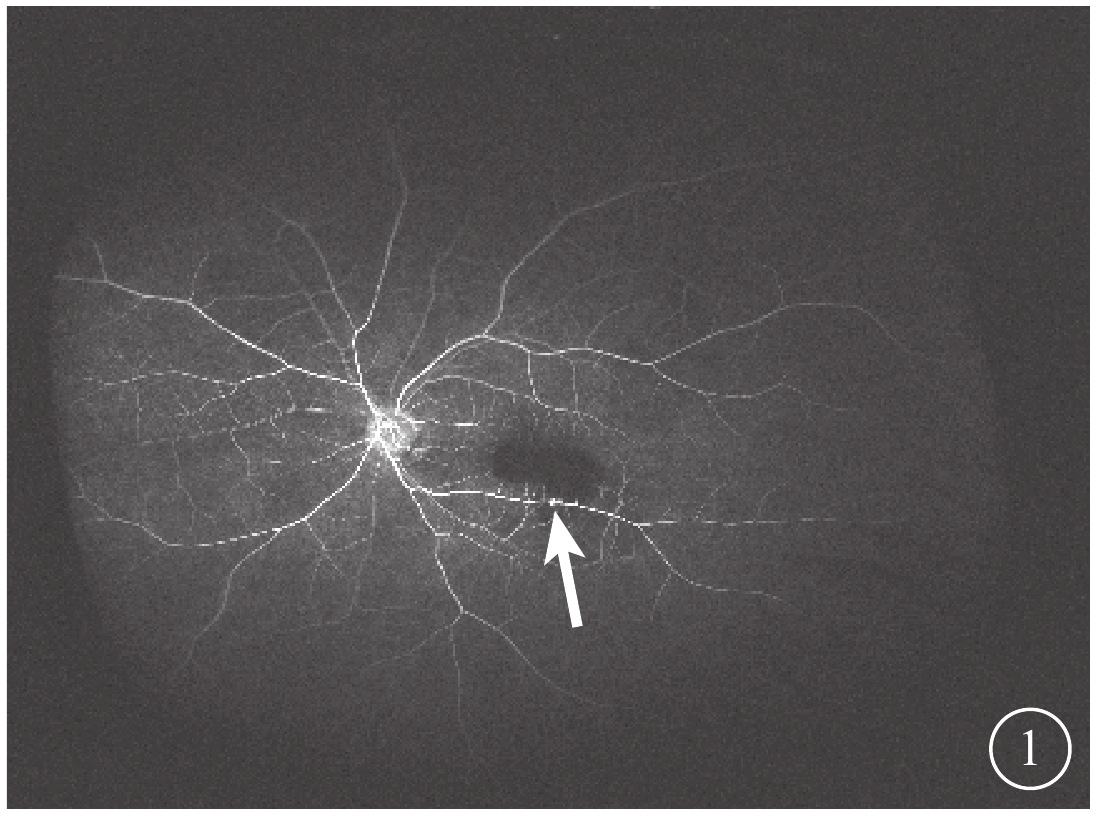

3只眼均行常規全身檢查及最佳矯正視力(BCVA)、眼壓、裂隙燈顯微鏡、眼底彩色照相、眼部B型超聲、熒光素眼底血管造影(FFA)及光相干斷層掃描(OCT)等眼部檢查。患眼BCVA為手動/20 cm~0.06,平均BCVA為0.03±0.02。眼壓為7.9~18.9 mmHg(1 mmHg=0.133 kPa),平均眼壓為(9.87±3.23)mmHg。3只眼均存在不同程度的晶狀體混濁。RAM位于視網膜顳上2只眼,位于視網膜顳下1只眼。黃斑區內界膜下出血大小為1.5~8.0倍視盤面積。FFA檢查發現,動脈期患眼顳下視網膜動脈分支處強熒光點,周圍出血遮蔽視網膜及脈絡膜熒光(圖1)。OCT檢查發現,患眼出血灶表面可見一弧形強反射條帶,且與內界膜相對應,其下呈點狀強反射(圖2)。

圖1

患眼FFA像。動脈期視網膜顳下可見強熒光點(白箭),上方出血遮蔽熒光

圖1

患眼FFA像。動脈期視網膜顳下可見強熒光點(白箭),上方出血遮蔽熒光

3只患眼經FFA檢查均可見動脈期顳側視網膜動脈分支處強熒光點,周圍出血遮蔽視網膜及脈絡膜熒光;OCT檢查可見出血灶表面一弧形強反射條帶,且與內界膜相對應,其下呈點狀強反射。證明其RAM及內界膜下出血診斷成立[5]。

3只眼均行常規全身檢查及最佳矯正視力(BCVA)、眼壓、裂隙燈顯微鏡、眼底彩色照相、眼部B型超聲、熒光素眼底血管造影(FFA)及光相干斷層掃描(OCT)等眼部檢查。患眼BCVA為手動/20 cm~0.06,平均BCVA為0.03±0.02。眼壓為7.9~18.9 mmHg(1 mmHg=0.133 kPa),平均眼壓為(9.87±3.23)mmHg。3只眼均存在不同程度的晶狀體混濁。RAM位于視網膜顳上2只眼,位于視網膜顳下1只眼。黃斑區內界膜下出血大小為1.5~8.0倍視盤面積。FFA檢查發現,動脈期患眼顳下視網膜動脈分支處強熒光點,周圍出血遮蔽視網膜及脈絡膜熒光(圖1)。OCT檢查發現,患眼出血灶表面可見一弧形強反射條帶,且與內界膜相對應,其下呈點狀強反射(圖2)。

圖1

患眼FFA像。動脈期視網膜顳下可見強熒光點(白箭),上方出血遮蔽熒光

圖1

患眼FFA像。動脈期視網膜顳下可見強熒光點(白箭),上方出血遮蔽熒光

3只患眼經FFA檢查均可見動脈期顳側視網膜動脈分支處強熒光點,周圍出血遮蔽視網膜及脈絡膜熒光;OCT檢查可見出血灶表面一弧形強反射條帶,且與內界膜相對應,其下呈點狀強反射。證明其RAM及內界膜下出血診斷成立[5]。